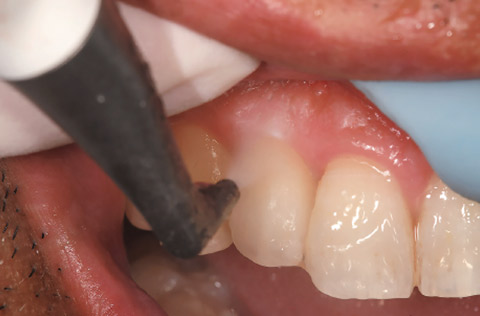

「ペリオフローノズル」の先端は軟らかく、歯牙の形態に沿って操作できる。プローブと同じ角度でポケット内に挿入できるため、隣接面へのアクセスも容易である(図18、19)。

歯周基本治療が終了し、残存した6〜7mm程度の縁下に対して使用することが多いが、1歯5秒以内でゆっくり細かく往復運動するようにデブラーキングすることにより、根面やインプラント周囲のバイオフィルムを除去していく(図21〜23)。

図18 縁下にプローブを挿入

図19 プローブと同じようにペリオフローノズルを縁下に挿入。